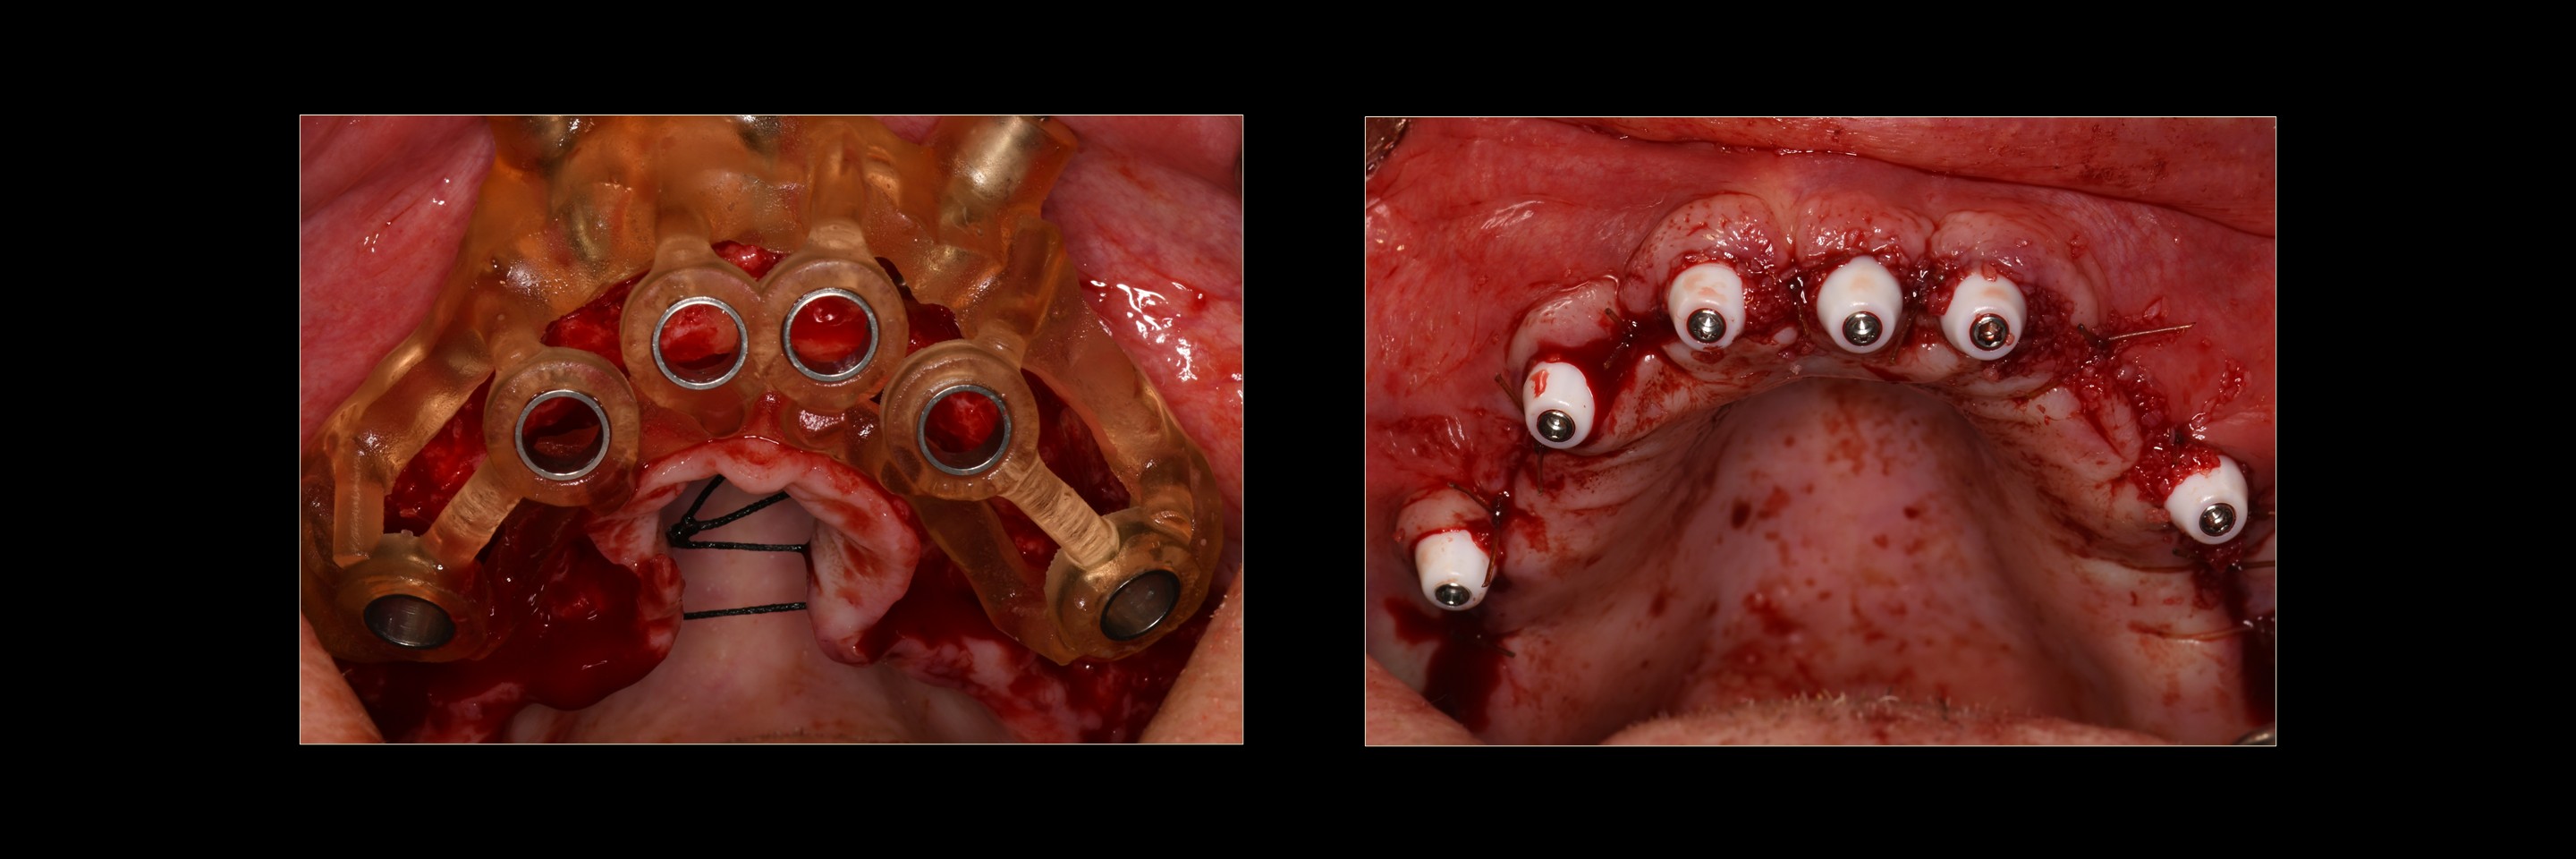

Director’s Clinical Cases

Director’s Clinical Cases